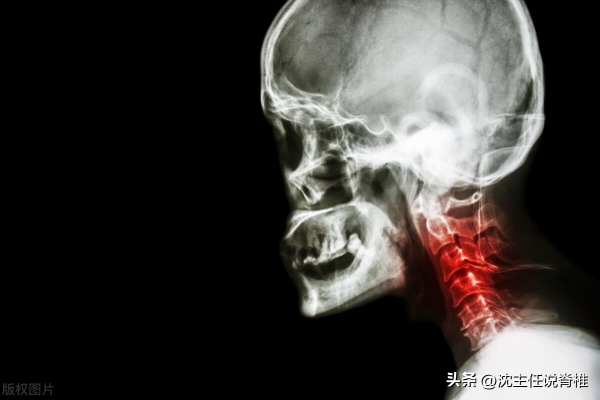

2、颈椎病

手指麻木伴随颈部僵硬、肩背酸痛,甚至转头时头晕目眩,可能是颈椎病的问题。

现在大家长期低头刷手机、伏案工作,颈椎承受的压力相当于头顶10公斤重物,导致颈椎间盘退变、骨质增生或韧带钙化,压迫神经根或脊髓。这种慢性压迫不仅引发手麻,还可能造成脑供血不足,增加中风风险。严重时,患者可能出现走路踩棉花感、大小便失禁等脊髓受损症状。